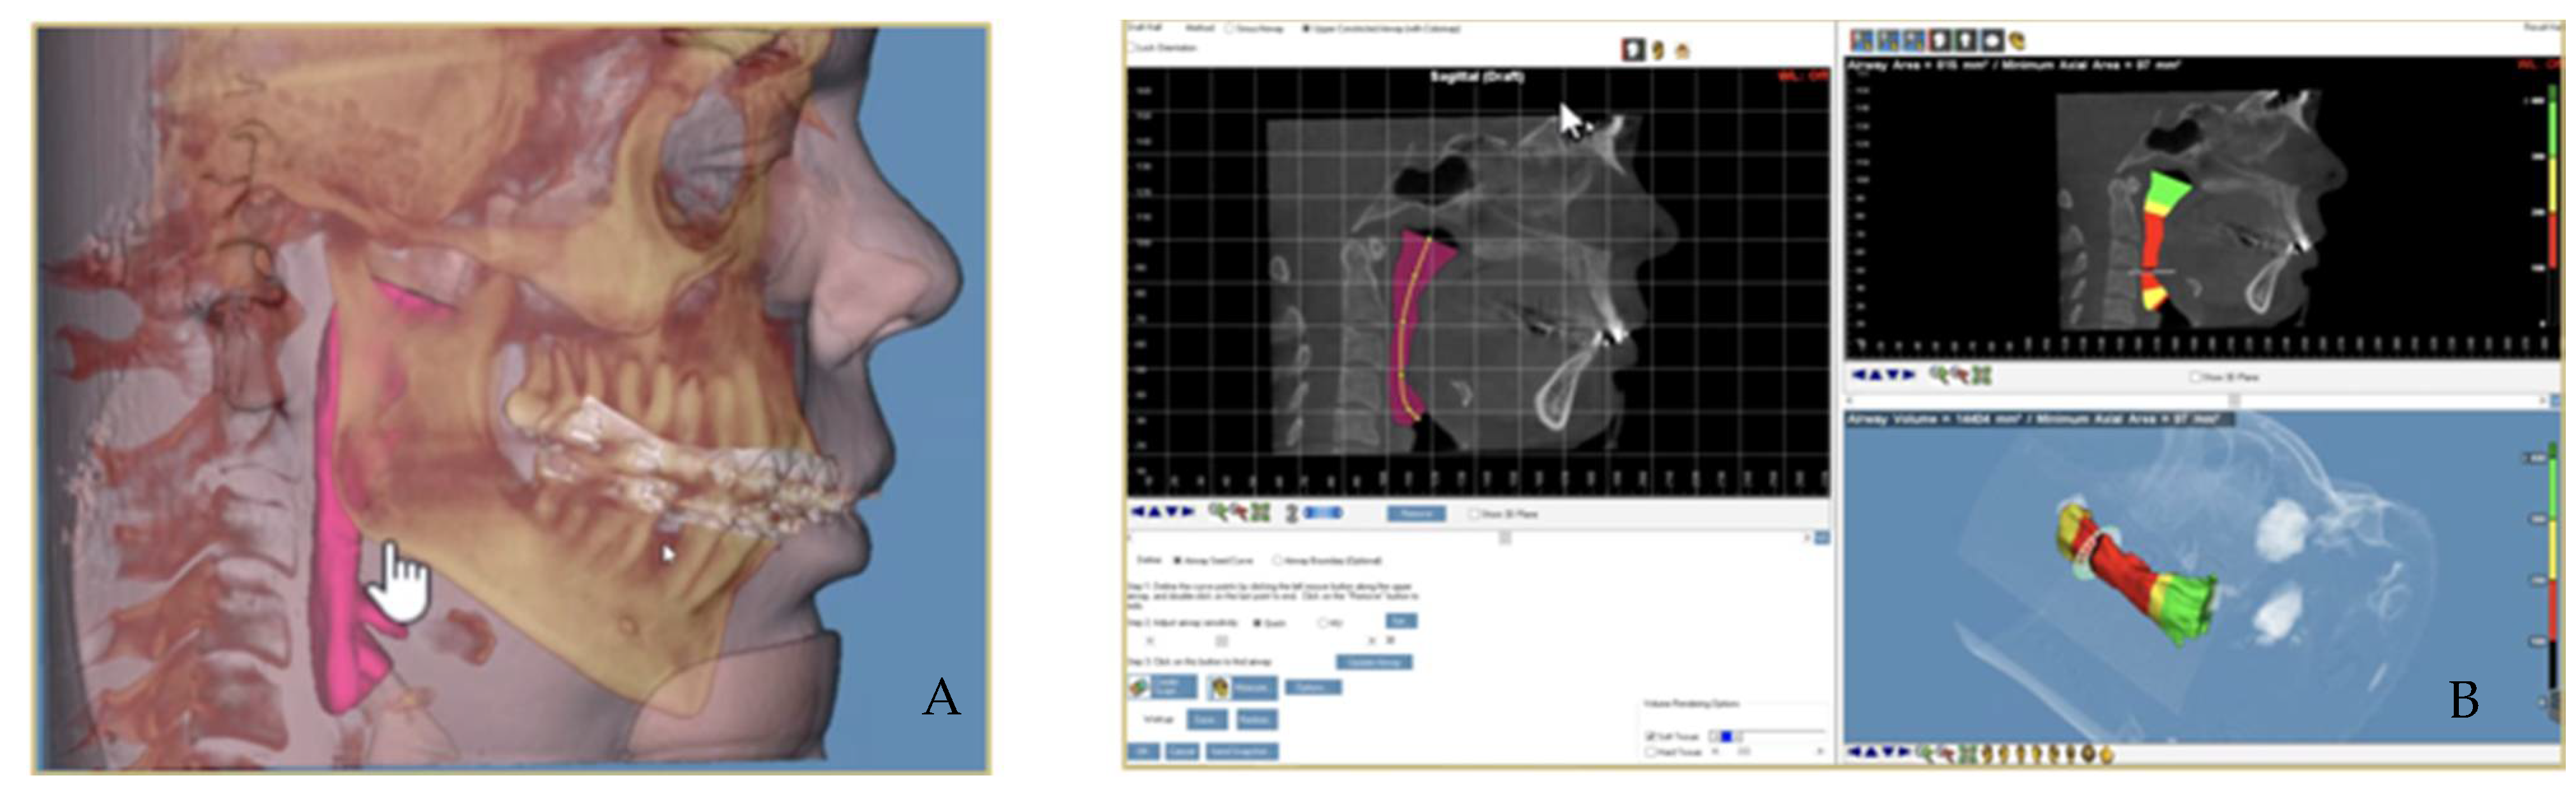

2.1.2. Airways Measuring Method with CBCT